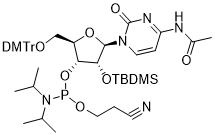

馬鞍山致研生物醫(yī)藥科技有限公司成立于馬鞍山市鄭浦港新區(qū)現(xiàn)代產(chǎn)業(yè)園。公司專(zhuān)注于生物小分子、醫(yī)藥中間體相關(guān)產(chǎn)品的研發(fā)和生產(chǎn),產(chǎn)品主要包括DNA亞磷酰胺單體、RNA亞磷酰胺單體、特殊單體以及按照客戶(hù)要求定制的RNA和DNA,并且公司提供定制合成等方面的研究服...

馬鞍山致研生物醫(yī)藥科技有限公司成立于馬鞍山市鄭浦港新區(qū)現(xiàn)代產(chǎn)業(yè)園。公司專(zhuān)注于生物小分子、醫(yī)藥中間體相關(guān)產(chǎn)品的研發(fā)和生產(chǎn),產(chǎn)品主要包括DNA亞磷酰胺單體、RNA亞磷酰胺單體、特殊單體以及按照客戶(hù)要求定制的RNA和DNA,并且公司提供定制合成等方面的研究服...